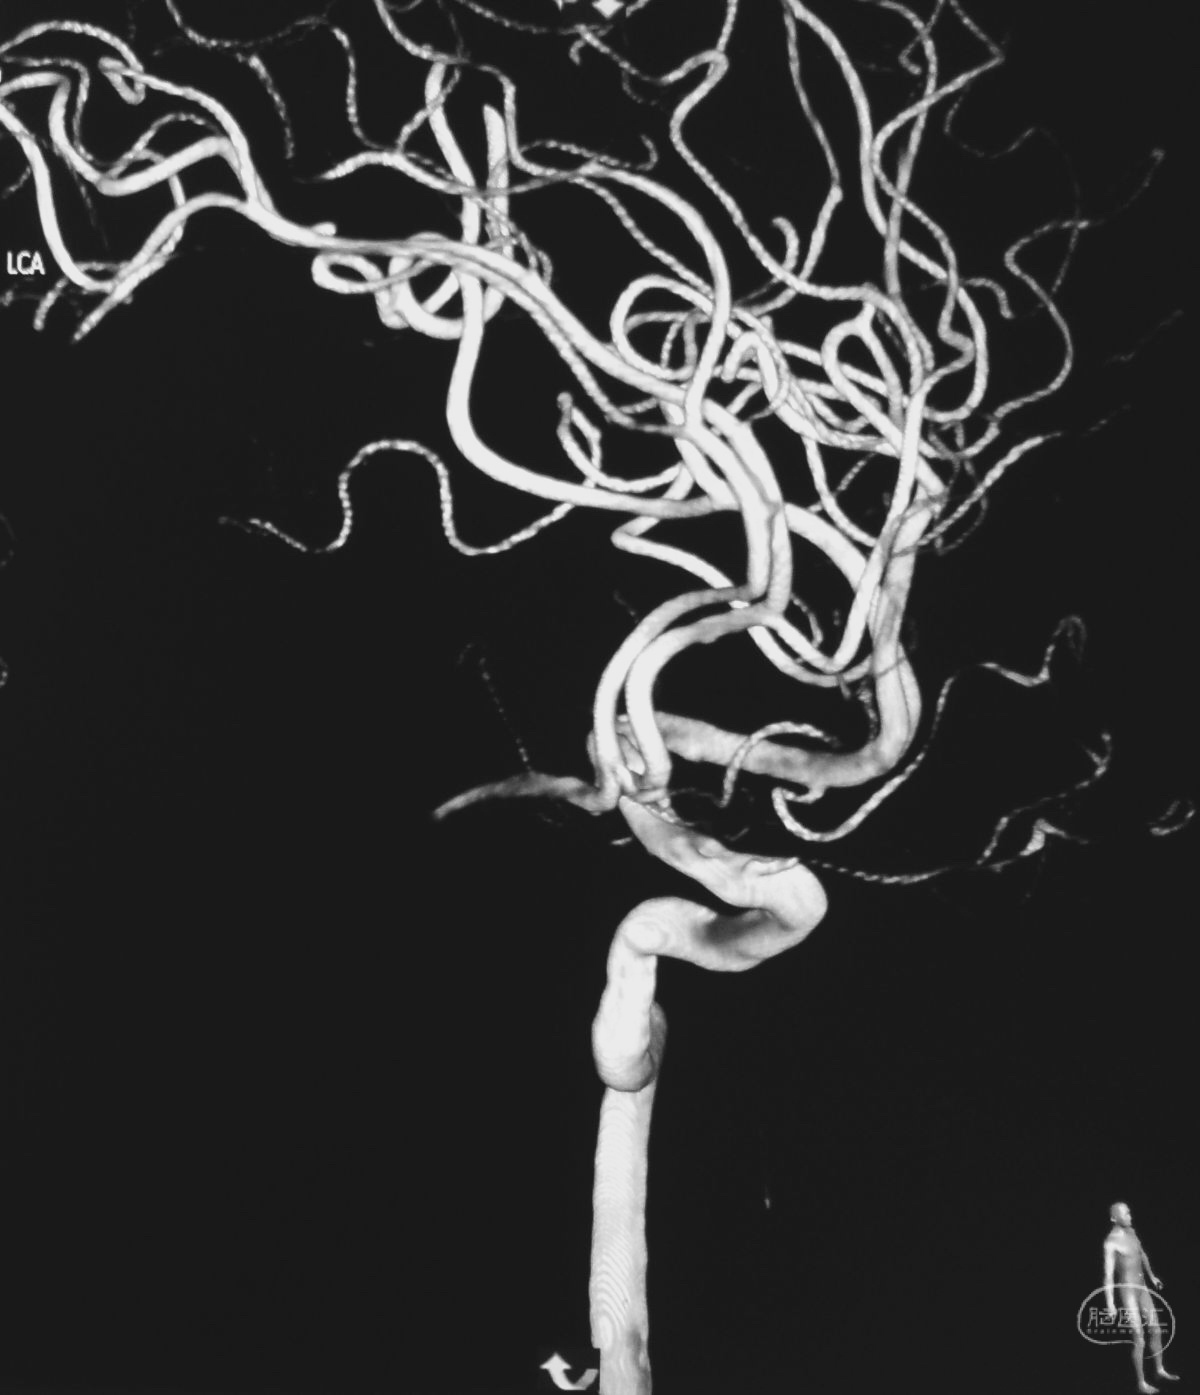

术后左颈内动脉造影三维重建显示动脉瘤消失。

病例二,右侧椎动脉V4段夹层动脉瘤,以头痛入院,21个月前有SAH史。

右椎动脉造影三维重建